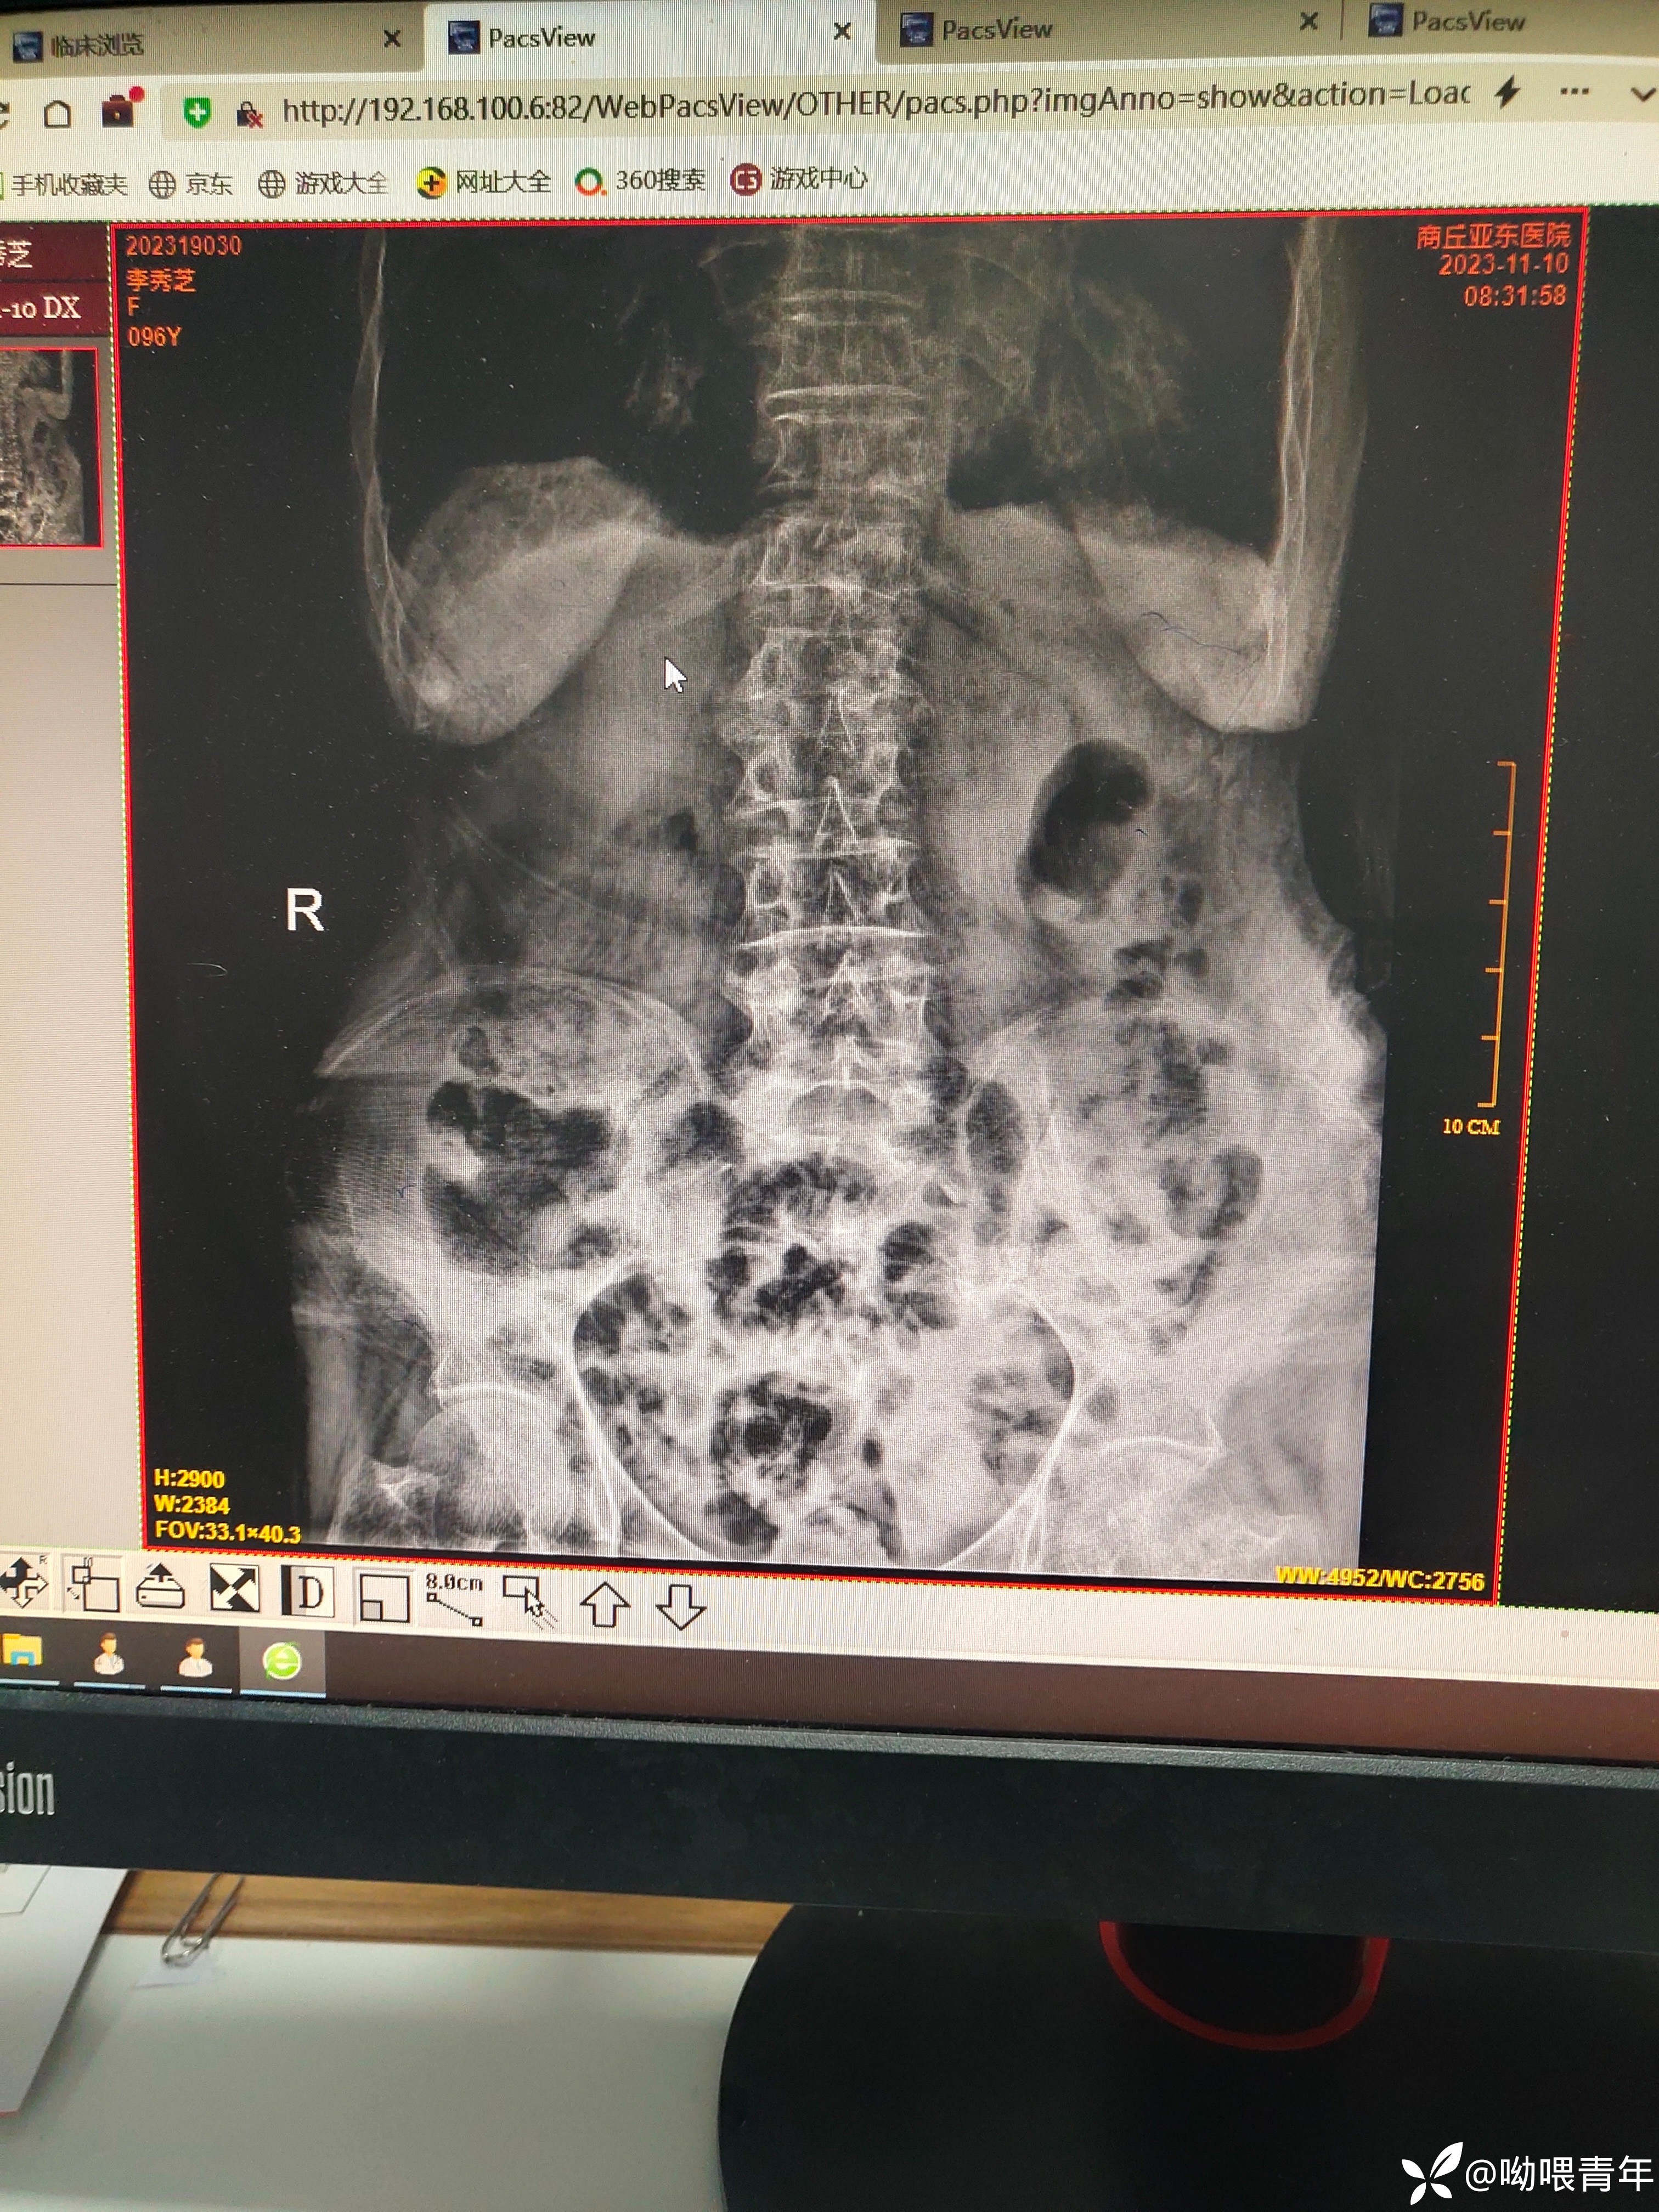

90多岁病人,右腹痛2天急诊入院,行上腹部CT检查提示:1.胆囊形态增大伴泥沙样结石;2.消化道穿孔可能。感染指标正常。查体:体温正常,查体腹肌紧张,右侧腹部轻压痛,无反跳痛。请各位老师帮忙分析一下。